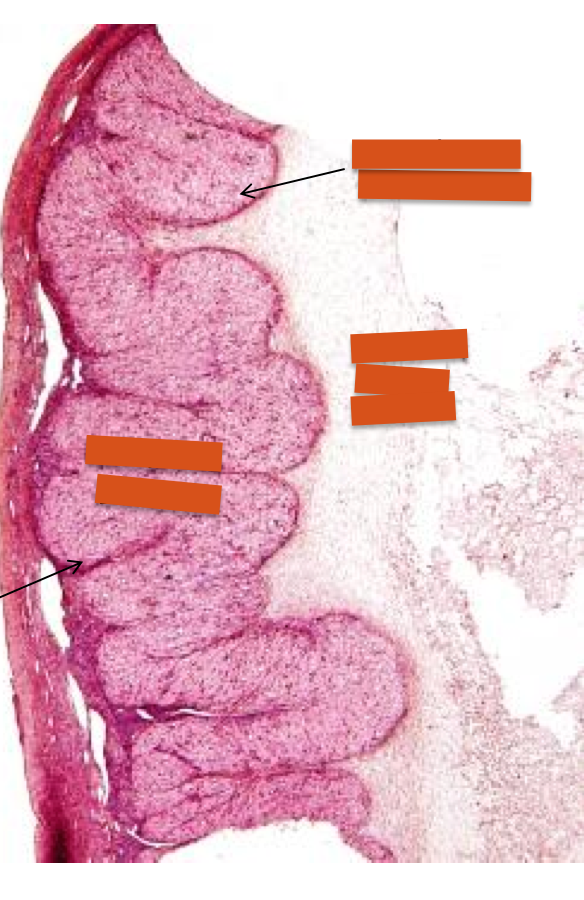

oviduct

oviduct plica